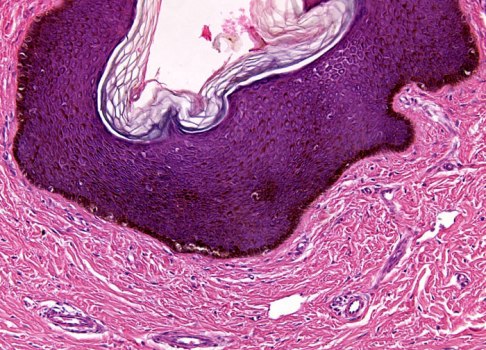

По данным визуального обследования - на левой кисти имеется рубцово-гипертрофированный участок кожи бордового цвета, размерами 2,0х1,0 см. Кожа вокруг рубца не изменена, болезненности при пальпации нет.

По данным гистологического исследования - многослойный эпителий с мифибробластами и гиализированным коллагеном (окраска гематоксилином), атипичных клеток не выявлено.